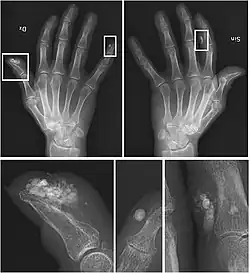

CREST syndrome (calcinosis and sclerodactyly) | |

CREST causes thickening and tightening of the skin with deposition of calcific nodules ("calcinosis").

Though it is the most easily recognizable manifestation, it is not prominent in all patients. Thickening generally only involves the skin of the fingers distal to the metacarpophalangeal joints in CREST. Early in the course of the disease, the skin may appear edematous and inflamed. Eventually, dermal fibroblasts overproduce extracellular matrix leading to increased tissue collagen deposition in the skin. Collagen cross-linking then causes a progressive skin tightening. Digital ischemic ulcers commonly form on the distal fingers in 30–50% of patients.[3]